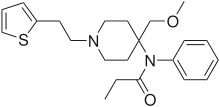

Anilidopiperidines

Phenylpiperidines